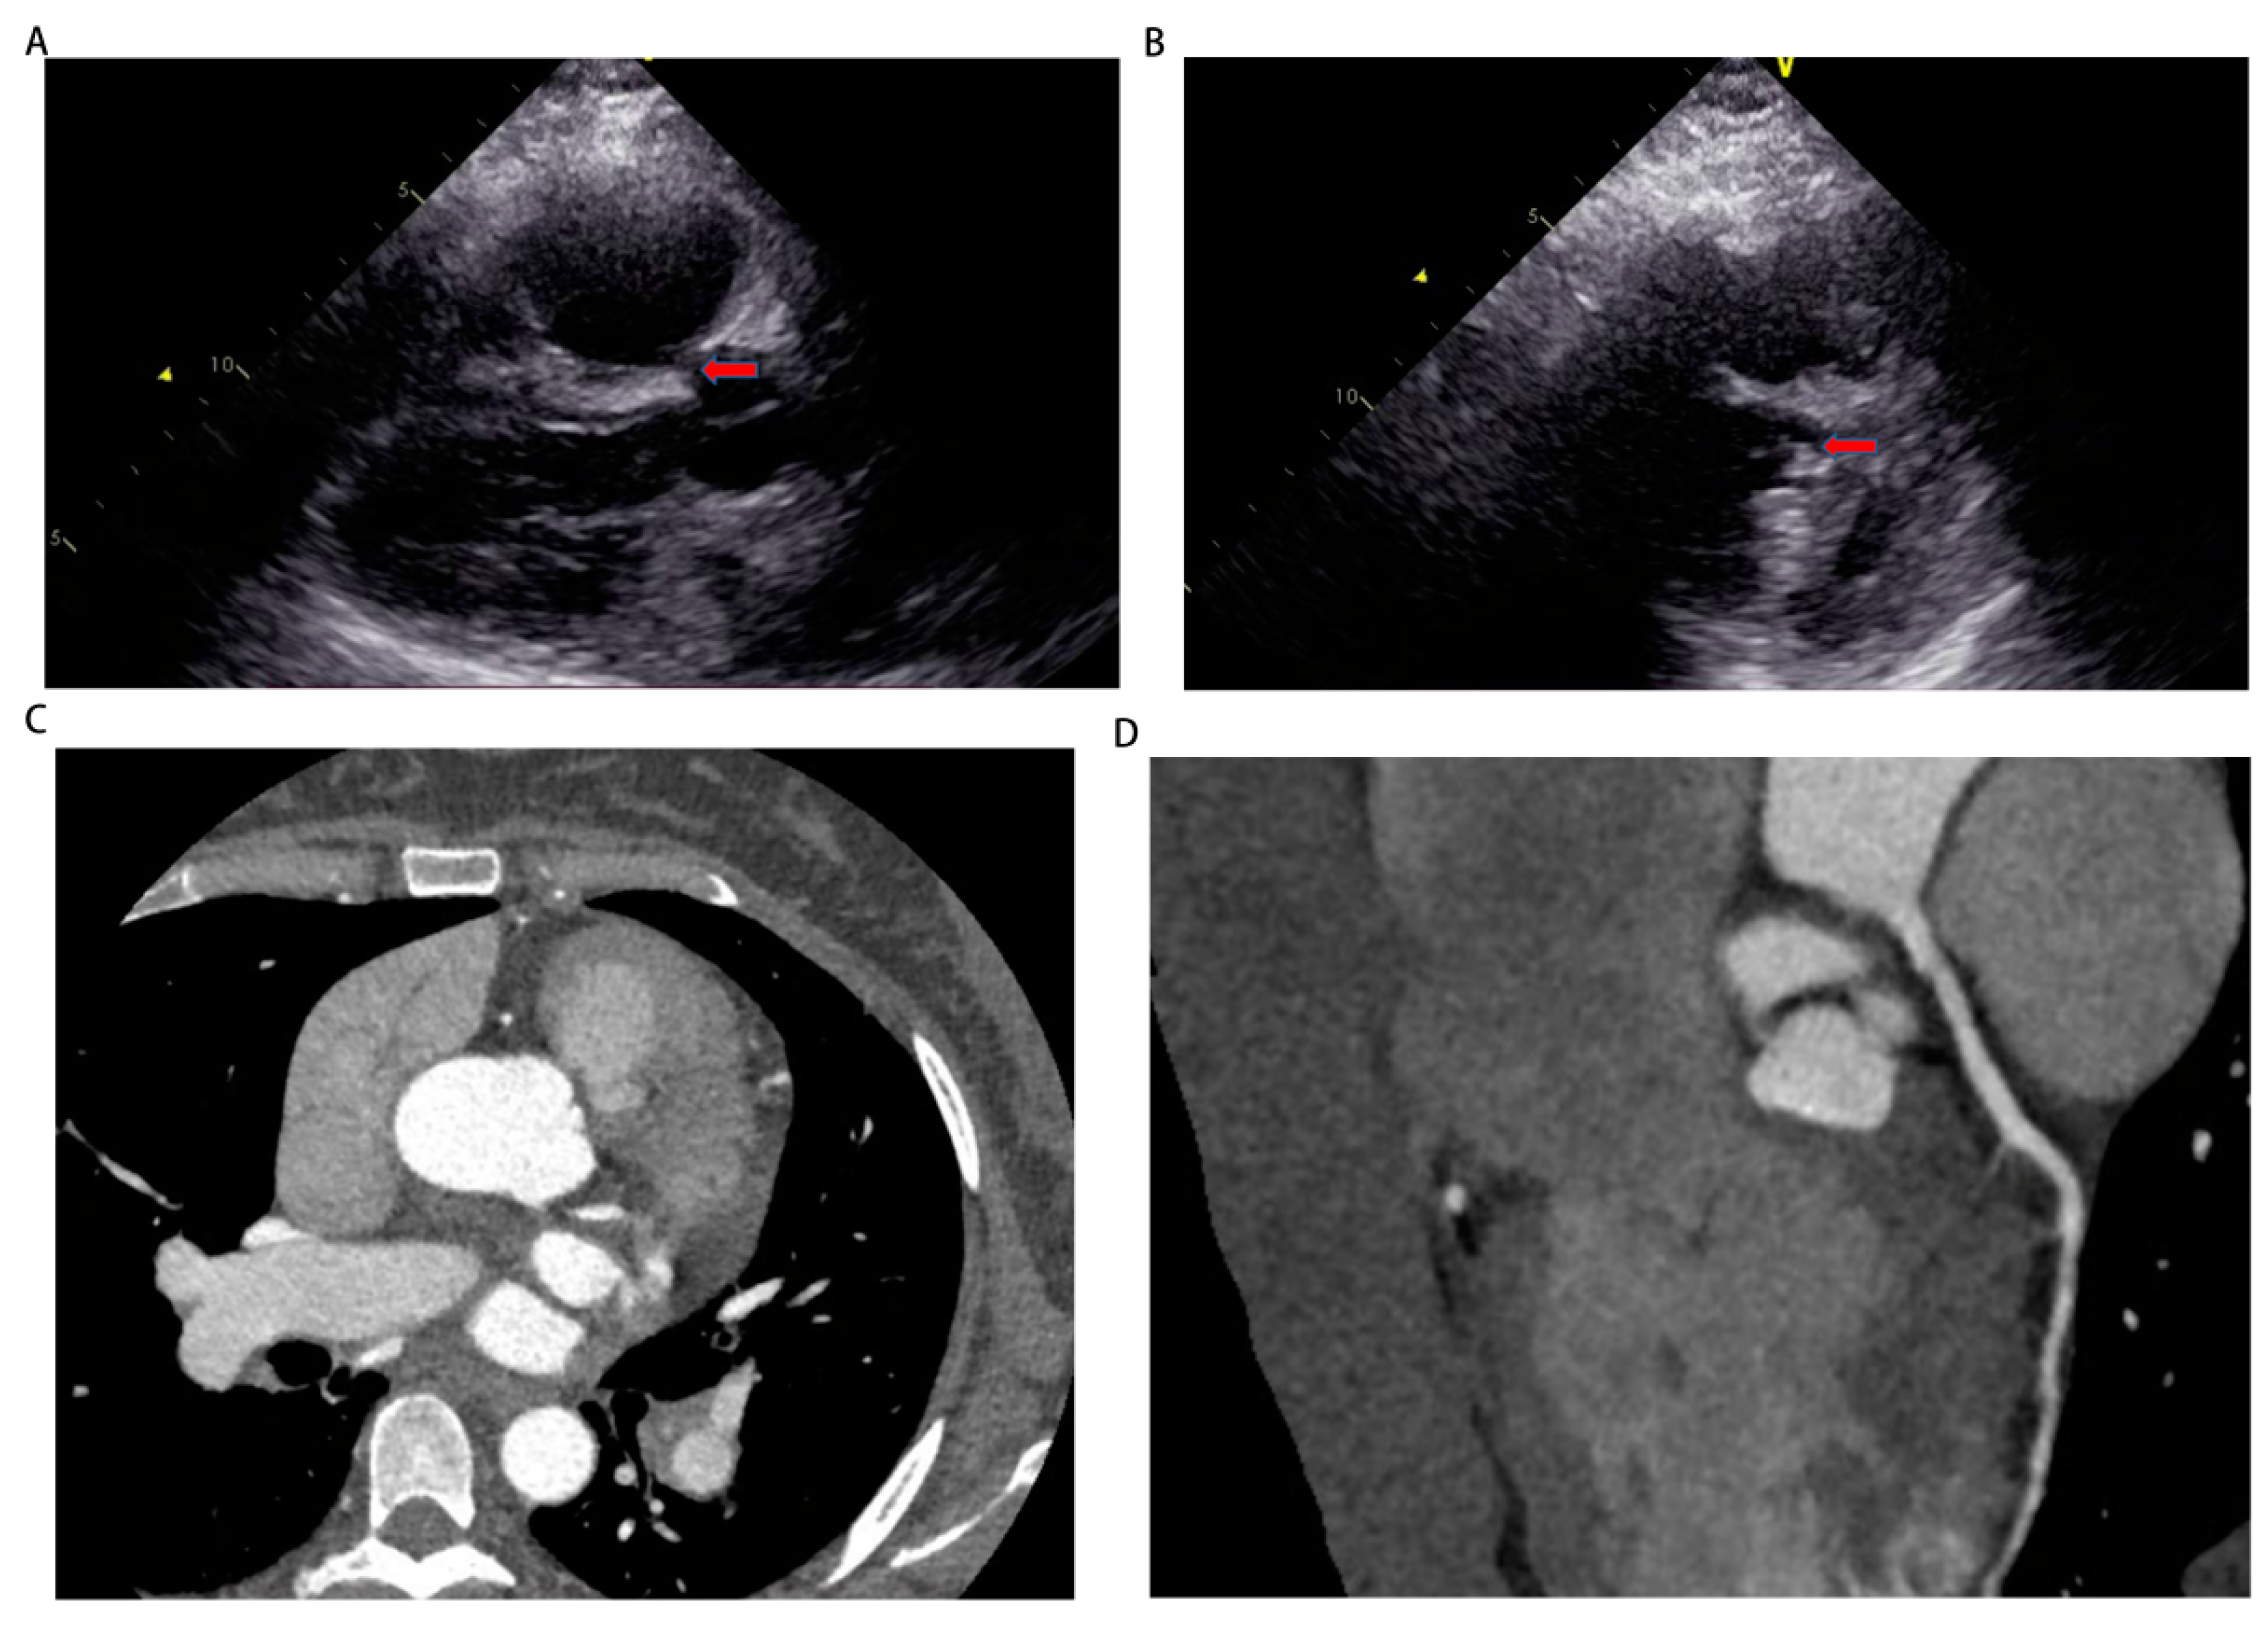

Figure 2. The images of pulmonary angiography and computed tomography pulmonary angiography. (A-C) The images of pulmonary angiography indicated the presence of pulmonary artery dilatation in left front tilt 30 degrees, right front tilt 30 degrees, forward and backward position 0 degree. (D, E) The images of computed tomography pulmonary angiography showed an enlargement of the pulmonary artery without any apparent filling defect.

On September 13th, we performed right heart catheterization and pulmonary angiography, yielding the following results: a baseline mean pulmonary artery pressure of 50 mmHg, a mean pulmonary artery pressure of 47 mmHg after inhalation of nitric oxide, a mean pulmonary capillary wedge pressure (PCWP) of 7 mmHg, a pulmonary vascular resistance of 19.99 woods units, and a cardiac output of 2.7 L/min (Figure 2A-C, Table 1 and Supplementary video 6-8). These findings align with the diagnosis of pre-capillary pulmonary hypertension. However, the repeat echocardiography on September 16th revealed a discontinuity of approximately 5mm in the upper part of the interventricular septum and subarterial ventrieular septal defect to be excluded (Figure 3A,B). Thus, we further refined cardiac CTA (Figure 3C,D and Supplementary video 11) then the results showed no obvious atrioventricular shunt or coronary artery stenosis. Combined with the pulmonary artery time delay angiography (Left front tilt 90 degrees, Supplementary video 9), no aorta to pulmonary artery or atrioventricular shunt was observed, we can basically rule out the possibility of pulmonary hypertension caused by congenital heart disease. Finally, it is also possible for this patient to suffer from toxic pulmonary hypertension as a result of her drug use. Nevertheless, given the long interval between drug use and patient onset, as well as the time this patient with no special discomfort, we eliminated toxin-induced pulmonary arterial hypertension.

Figure 3. The images of echocardiography and cardiac computed tomography angiography. (A, B) Echocardiography on September 16th showed a discontinuity of approximately 5 mm in the upper part of the interventricular septum and subarterial ventrieular septal defect to be excluded. (C, D) Cardiac computed tomography angiography showed no obvious atrioventricular shunt or coronary artery stenosis.

The patient's manifestation of dyspnea and hypoxemia following a cesarean section, resembling the clinical symptoms of pulmonary embolism, which possibly suggests the occurrence of microthrombosis and subsequent obstruction of micro branches within the pulmonary vessel during the early stages of the disease (10). Therefore, the possibility of pulmonary embolism was not disregarded and a thorough examination was conducted utilizing a range of diagnostic methodologies, namely pulmonary perfusion imaging, CTPA, and pulmonary angiography. The results obtained from the pulmonary perfusion imaging revealed the presence of multiple areas with impaired blood perfusion in both lungs, with a particular emphasis on the left lung. Conversely, both CTPA and pulmonary angiography did not provide any conclusive evidence of thrombus formation. Consequently, the diagnosis of pulmonary embolism was excluded and it was postulated that this phenomenon was linked to pulmonary vasoconstriction (11).